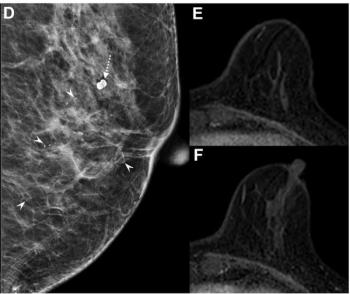

For HER2-positive breast cancer patients with radiologic complete response on breast MRI after neoadjuvant chemotherapy (NAC), the absence of calcifications was associated with over a 13 percent higher positive predictive value (PPV) for pathologic complete response (pCR).